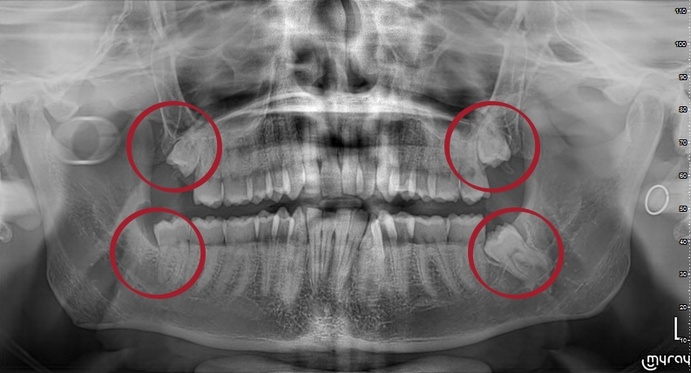

Спочатку роблять панорамний знімок, який допоможе визначити стан зубів: довжину коренів та їх форму, відстань до гайморової пазухи та нерва. При частковому прорізуванні зуба знімок покаже, скільки кісткової тканини знаходиться над його коронкою. Це допоможе спланувати атипове видалення зубів мудрості та успішно провести операцію.